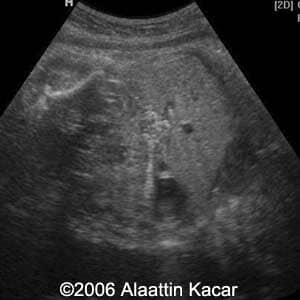

Gallstones Alaattin Kacar, MD Sureyya Paksoy MD Burhan Seker, MD Ender Birgul, MD Article Published: Jun 8, 2006 Balikesis, Turkey These are several images of a fetus with multiple gallstones Discussion Board Start a discussion about this article Add to Favorites Favorite